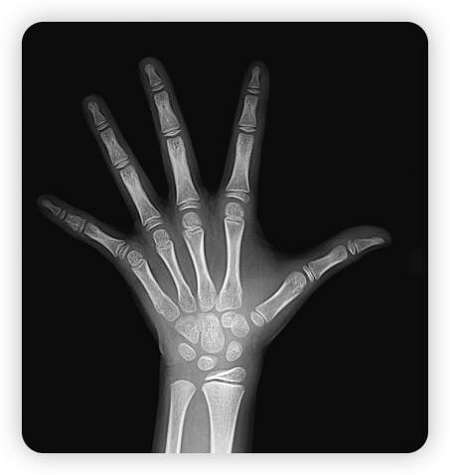

骨骺线完全闭合状态